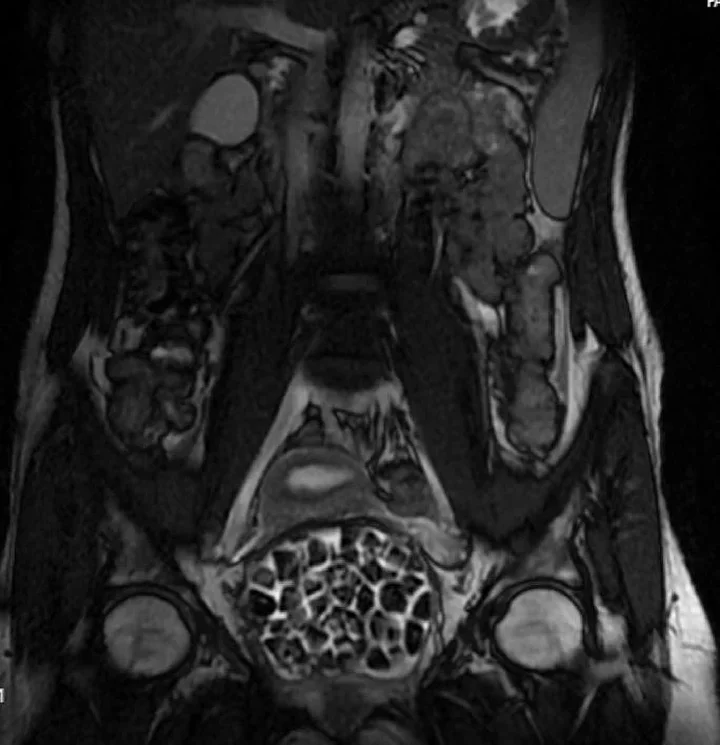

Hastasının durumuna yönelik konuşan Üroloji Uzmanı Doç. Dr. Erkan Erkan, "Hastamızın 2004 yılında doğduğunu ardından doğar doğmaz ekstrofi vezika dediğimiz 50 binde bir görülen bir anomaliden dolayı art arda ameliyatlar geçirdiğini öğrendik. 10 yaşında yine bir ameliyat geçirmişti, gerekli görüntüleme ve tetkiklerimizi yaptırdık. Normalde mesanesinin olması gereken yerin hemen arka kısmında taşlarla dolu bir kese olduğunu gördük, bunun üzerine ek görüntülemeler; MR çektirdik. Hastamız çelişkili açıklamalar almıştı, kendi radyolojik kliniğimiz ve edindiğimiz konsültasyonlarda taşların mesanede değil vajinal boşlukta oluştuğunu düşündük, bir planlama yaptık.

Kadın doğum hocamızın da çabasıyla taşları tamamen temizledik ardından ileride normal bir hayat sürmesi bakımından oraya plastik cerrahi yaptık. 287 adet taş çıkardık, pratikte gerçekten görünce çok şaşırdık çünkü bu aynı zamanda literatürde çok nadir görülen bir olay. Biz ameliyata hazırlanırken de teorik olarak biraz araştırdık. Literatürde gördüğümüz kadarıyla buna benzer bu tanıma uyan bir vaka vardı. Literatürde sanırım yayınlanmış 2’nci vaka olacak. Farkındalık çok önemli, bilinçli bir hastamız vardı. Doğumsal anomaliyle doğan çocuklarımızda ileride bunlara bağlı bazı sıkıntılar çıkabileceğinin öngörülmesi lazım. İlgili tedavilerini alsalar bile düzenli takiplere gelmeleri gerekiyor. İleride eğer dikkat etmezse ki zannetmiyorum, tekrarlayabilir. Bu rahatsızlık ekstrofi vezikal epispadias durumu çok nadir bir durum" dedi.

Genç kızın uzun süredir devam eden karın ağrısı olduğunu söyleyerek sözlerine başlayan Jinekolojik Onkoloji Uzmanı Op. Dr. Emin Erhan Dönmez, "Mesane taşları olduğu düşünülerek daha büyük bir hastaneye refere edilmiş. Aramızda mini bir konsey yaparak muayene ettik. Vajen bir hazne görevi görerek orada durağan bir idrar, uzun süre beklediği için idrar içindeki minerallerde çökerek taşlar oluşmuş. Mesanedeki idrarın vajene akmış olabileceği ve vajende göllenen idrar nedeniyle taşların burada oluşacağını düşündük, ameliyatımızı planladık. Ameliyata tanı amaçlı girmiştik, sistoskopi (Mesane gibi idrar yollarını kapsayan kısımlardaki rahatsızlıkların teşhis ve tedavisinde kullanılan endoskopik bir yöntem) dediğimiz ameliyatı Erkan Hocam ile birlikte gerçekleştirdik.

Önce mesaneyi bir görüntüledik, mesane tabanına yaklaşık 2-3 cm’lik bir alandan vajene fistülize olduğunu gördük. Mesaneden vajene geçtiğimiz esnada tüm vajenin taşlarla dolu olduğunu gördük. Tanı amacıyla girdiğimiz ameliyatta her şey de olağan gittiği için tedaviye geçtik. Taşların çıkabileceği kadar bir genişlik sağladık. Daha sonra yaklaşık en büyüğü 2,5 cm boyutlarında olan, irili ufaklı 287 tane taşı ameliyat esnasında çıkarmış olduk. Taşların tekrarlamaması için idrarın göllenmemesi, en azından dışarıya rahatça boşalabilmesi için vajinal rekonstrüksiyonu sağladık. Ameliyatta da herhangi bir problem yaşamadık. Literatürü Erkan Hocam ile birlikte değerlendirmiştik. Primer olarak vajende birikmiş olan bu kadar çok sayıda taşla ilgili bir makale görmedik, rastlamadık" dedi.